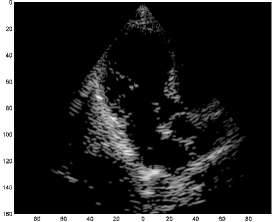

In this section, we examine results obtained by applying our Xampling schemes, illustrated in Figs. 4 and 6, to raw RF data, acquired and stored for cardiac images of a healthy consenting volunteer. The acquisition was performed using a GE breadboard ultrasonic scanner of 64 acquisition channels. The transducer employed was a 64-element phased array probe, with central frequency, operating in second harmonic imaging mode: 3 half cycle pulses are transmitted at , resulting in a signal characterized by a rather narrow bandpass bandwidth, centered at . The corresponding second harmonic signal, centered at , is then acquired. The signal detected in each acquisition channel is amplified and digitized at a sampling-rate of . Data from all channels were acquired along 120 beams, forming a sector, where imaging to a depth of , we have . The imaging results are illustrated in Fig. 11.

The first image (a) was generated using the standard technique, applying beamforming to data first sampled at the Nyquist-rate, and then down-sampled, exploiting its limited essential bandwidth. For a single scanline, sampling at , we acquire real-valued samples from each element, which are then down-sampled, to real-valued samples, used for beamforming. The resulting image is used as reference, where our goal is to reproduce the macroscopic reflectors observed in this image with our Xampling schemes.

We begin by applying the scheme illustrated in Fig. 4, utilizing the analog kernels defined in (23). Modulation with the kernels is simulated digitally. Assuming reflectors, and using two-fold oversampling, comprises consecutive indices. With such selection, the corresponding frequency samples practically cover the essential spectrum of . Since each sample is complex, we get an eight-fold reduction in sample-rate. Having estimated the Fourier series coefficients of , we obtain its parametric representation by solving (40) using OMP. We then reconstruct according to (31), that is we apply phase shifts to the modulated pulses, based on the extracted coefficients’ phases. The resulting image (b) depicts the strong perturbations observed in (a). Moreover, isolated reflectors at the proximity of the array () remain in focus.

We next apply the approximated scheme, illustrated in Fig. 6: for every , and , we find and of (26) such that . This process is performed numerically, off-line, based on our imaging setup. Consequently, we construct off-line, according to (30). Choosing this level of approximation, we end up with a seven-fold reduction in sample rate, where, for the construction of a single scanline, an average of complex samples must be taken from each element. We point out that in this scenario, the maximal number of samples, taken from certain elements, reaches for specific values of . Thus, if a common rate is to be used for all sensors, for all values of , we may still achieve a six-fold reduction in sample rate. As before, we use OMP in order to obtain ’s parametric representation, and reconstruct it based on our generalized FRI model proposed in (31). The resulting image (c) appears very similar to (b).